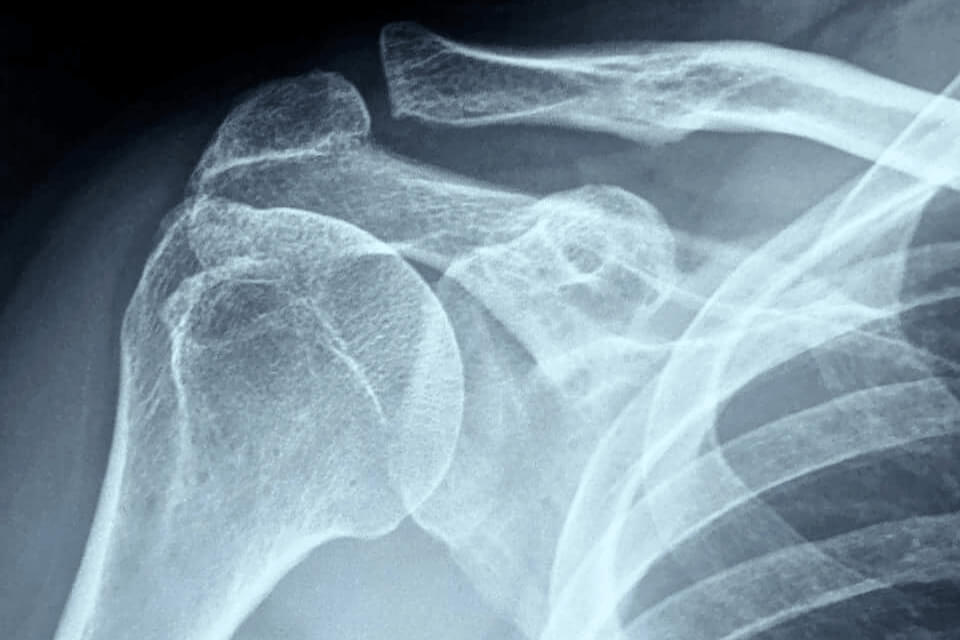

- рентген плечевого сустава в 2-х проекциях для выявления возможных сопутствующих повреждений, дегенеративных изменений;